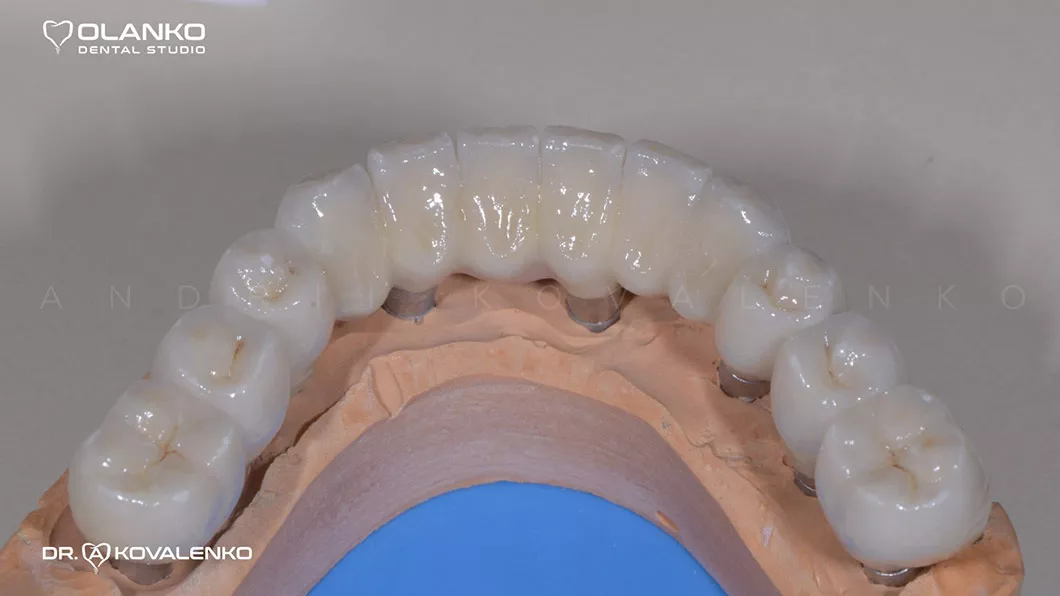

Вид готовых керамических коронок и мостовидных протезов

Клинический случай 1 имплантация зубов